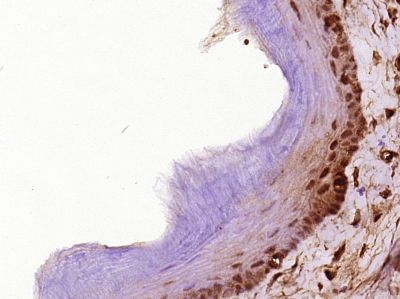

| 产品图片 | ![]() Sample: Mcf-7(Human) Cell Lysate at 30 ug Primary: Anti-Cyclin D1 (bs-0623R) at 1/300 dilution Secondary: IRDye800CW Goat Anti-Rabbit IgG at 1/20000 dilution Predicted band size: 32 kD Observed band size: 32 kD ![]() Sample: A549 Lysate at 40 ug Primary: Anti-CyclinD1 (bs-0623R) at 1/300 dilution Secondary: IRDye800CW Goat Anti-Rabbit IgG at 1/10000 dilution Predicted band size: 32 kD Observed band size: 35 kD ![]() Sample: A549 Cell (Human) Lysate at 30 ug Primary: Anti-Cyclin D1 (bs-0623R) at 1/300 dilution Secondary: IRDye800CW Goat Anti-Rabbit IgG at 1/20000 dilution Predicted band size: 32 kD Observed band size: 35 kD ![]() Paraformaldehyde-fixed, paraffin embedded (Rat liver); Antigen retrieval by boiling in sodium citrate buffer (pH6.0) for 15min; Block endogenous peroxidase by 3% hydrogen peroxide for 20 minutes; Blocking buffer (normal goat serum) at 37°C for 30min; Antibody incubation with (Cyclin D1) Polyclonal Antibody, Unconjugated (bs-0623R) at 1:400 overnight at 4°C, followed by operating according to SP Kit(Rabbit) (sp-0023) instructionsand DAB staining. ![]() Paraformaldehyde-fixed, paraffin embedded (Rat esophageal); Antigen retrieval by boiling in sodium citrate buffer (pH6.0) for 15min; Block endogenous peroxidase by 3% hydrogen peroxide for 20 minutes; Blocking buffer (normal goat serum) at 37°C for 30min; Antibody incubation with (Cyclin D1) Polyclonal Antibody, Unconjugated (bs-0623R) at 1:400 overnight at 4°C, followed by operating according to SP Kit(Rabbit) (sp-0023) instructionsand DAB staining. ![]() Paraformaldehyde-fixed, paraffin embedded (Rat testis); Antigen retrieval by boiling in sodium citrate buffer (pH6.0) for 15min; Block endogenous peroxidase by 3% hydrogen peroxide for 20 minutes; Blocking buffer (normal goat serum) at 37°C for 30min; Antibody incubation with (Cyclin D1) Polyclonal Antibody, Unconjugated (bs-0623R) at 1:400 overnight at 4°C, followed by operating according to SP Kit(Rabbit) (sp-0023) instructionsand DAB staining. ![]() Paraformaldehyde-fixed, paraffin embedded (Human cervical cancer); Antigen retrieval by boiling in sodium citrate buffer (pH6.0) for 15min; Block endogenous peroxidase by 3% hydrogen peroxide for 20 minutes; Blocking buffer (normal goat serum) at 37°C for 30min; Antibody incubation with (Cyclin D1) Polyclonal Antibody, Unconjugated (bs-0623R) at 1:400 overnight at 4°C, followed by operating according to SP Kit(Rabbit) (sp-0023) instructionsand DAB staining. ![]() Tissue/cell: human endometrium carcinoma; 4% Paraformaldehyde-fixed and paraffin-embedded; Antigen retrieval: citrate buffer ( 0.01M, pH 6.0 ), Boiling bathing for 15min; Block endogenous peroxidase by 3% Hydrogen peroxide for 30min; Blocking buffer (normal goat serum,C-0005) at 37℃ for 20 min; Incubation: Anti-Cyclin D1 Polyclonal Antibody, Unconjugated(bs-0623R) 1:200, overnight at 4°C, followed by conjugation to the secondary antibody(SP-0023) and DAB(C-0010) staining ![]() Tissue/cell: human placenta tissue; 4% Paraformaldehyde-fixed and paraffin-embedded; Antigen retrieval: citrate buffer ( 0.01M, pH 6.0 ), Boiling bathing for 15min; Block endogenous peroxidase by 3% Hydrogen peroxide for 30min; Blocking buffer (normal goat serum,C-0005) at 37℃ for 20 min; Incubation: Anti-Cyclin D1 Polyclonal Antibody, Unconjugated(bs-0623R) 1:200, overnight at 4°C, followed by conjugation to the secondary antibody(SP-0023) and DAB(C-0010) staining ![]() Blank control: RSC96(blue), the cells were fixed with 2% paraformaldehyde (10 min) and then permeabilized with ice-cold 90% methanol for 30 min on ice. Isotype Control Antibody: Rabbit IgG(orange) ; Secondary Antibody: Goat anti-rabbit IgG-PE(white blue), Dilution: 1:200 in 1 X PBS containing 0.5% BSA ; Primary Antibody Dilution: 1μg in 100 μL1X PBS containing 0.5% BSA(green). |